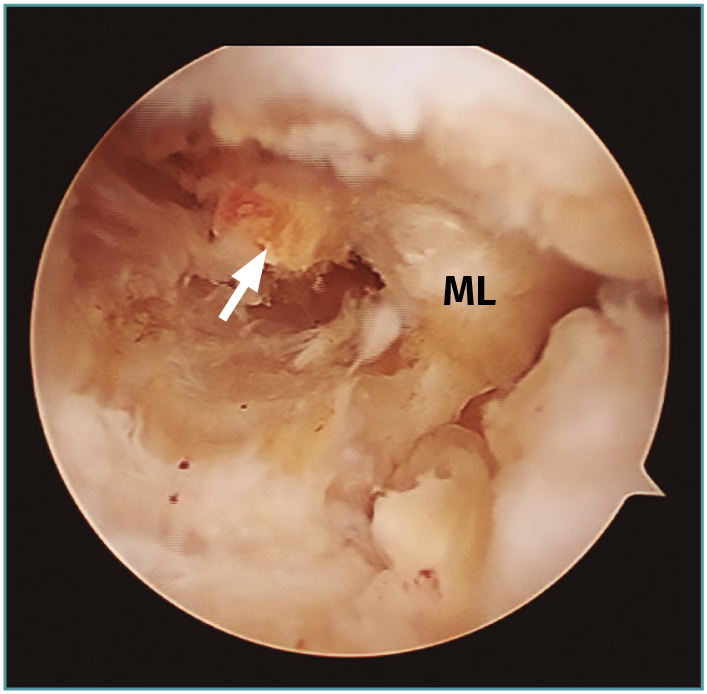

Se considera lesión de la raíz a la avulsión de la misma del hueso con o sin fragmento óseo (Figura 1), o bien a la rotura (normalmente radial) de la región adyacente al mismo (< 1 cm) (Figura 2)(3). Esta puede ser de naturaleza degenerativa o traumática (generalmente asociada a lesiones ligamentosas de la rodilla).

Figura 1. Avulsión de la raíz posterior del menisco lateral (ML) con fragmento óseo (flecha: fragmento óseo avulsionado).